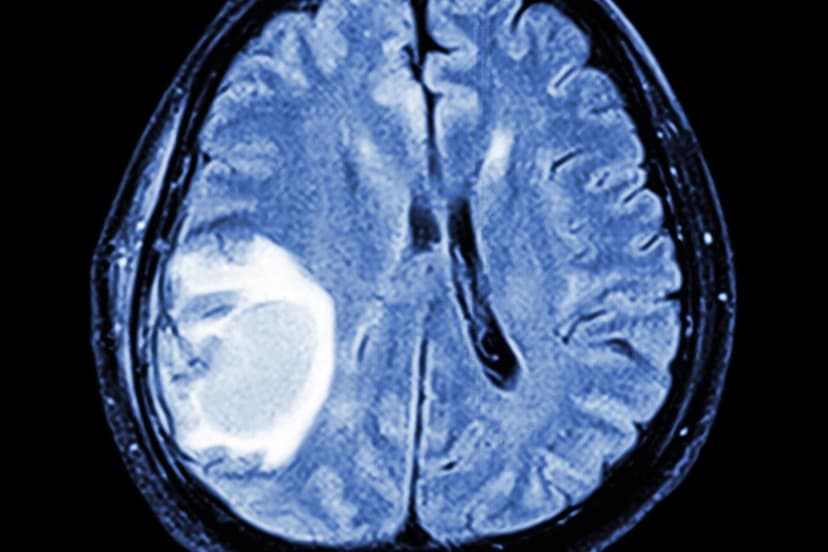

The distinction between a tumor and cancer is frequently misunderstood, leading to confusion among the public and even healthcare professionals. A tumor is any abnormal swelling, which can be benign (non-cancerous) or malignant (cancerous). Benign tumors, like lipomas, are often harmless, though some, such as uterine fibroids, can cause issues due to their location.

Cancer arises from genetic mutations that allow cells to grow unchecked and evade the body's defenses. Key characteristics of cancer include invasion of surrounding tissues and metastasis, or spreading to distant sites. While solid cancers often form masses, blood cancers like leukemia do not typically present as tumors.

Accurate communication is essential, as the terms 'tumor' and 'cancer' carry different implications for prognosis and treatment. Misusing these terms can lead to significant patient anxiety. Understanding whether a growth is benign or malignant, confirmed by pathology, dictates the urgency and complexity of management, which can range from simple removal to intensive therapies.